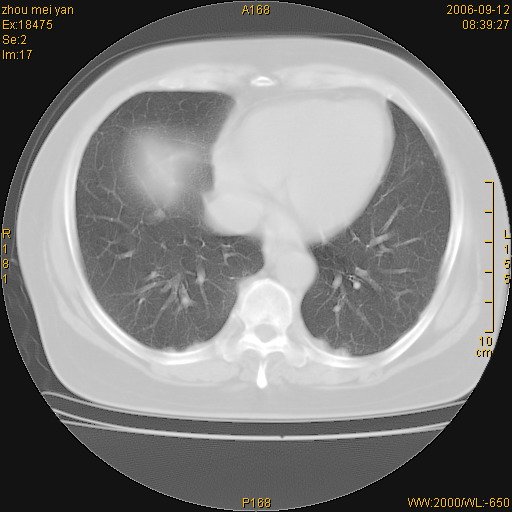

患者、女、55岁。因心率失常住院检查ct发现胸部多发结节。腹部b超肝、胆、胰、脾、肾、子宫附件未见异常。无结核病史,无粉尘接触史。请大家来会诊。谢谢!

病变位于胸膜,多发结节,边界清楚,内见小结节状钙化。其它未见异常。

双侧胸膜多发结节,形态不规则,边缘较清楚,每一个结节中心似乎都有钙化点的特征,与胸膜广基相切。临床无结核病史,无粉尘接触史。

影像表现十分有特点:双侧肋胸膜及膈胸膜广泛散在分布大小在2至6mm左右,较大病灶中心可见钙化。

考虑恶性胸膜间皮瘤可能性大,病灶位于胸膜,以宽基地与胸膜相连,呈结节样改变,部分病灶内可见点状钙化影。请各位老师多多指导!

双侧肋胸膜及膈胸膜广泛散在分布大小不等结节影,较大病灶中心可见钙化。